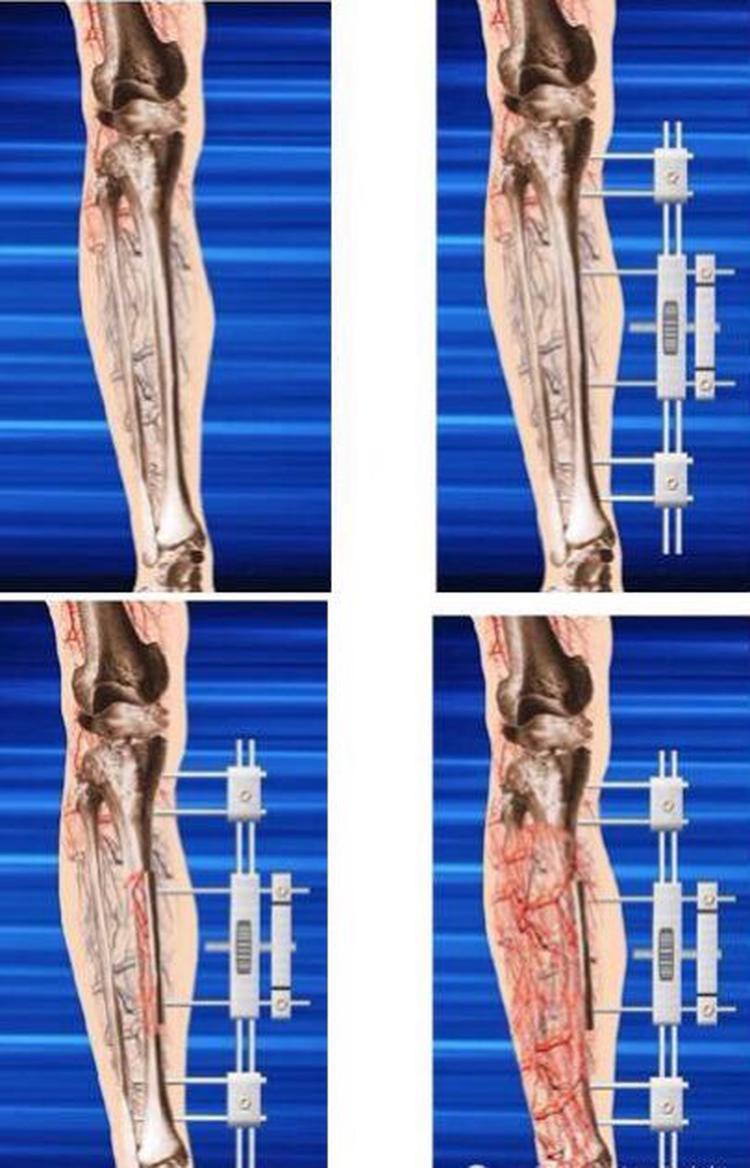

赵占富主任团队应用目前国内外流行的先进新技术,在我市首次采用胫骨微创横向骨搬移对患者下肢血管病变进行治疗,在迁移的过程中下肢毛细血管组织重新建立,从根源上改善由于肢体血供不足所导致的远端组织缺血坏死。

骨搬移技术治疗糖尿病足,是用小腿上的胫骨(粗骨)"开窗"一块,每天缓慢的一个mm横向拉,形成大量骨痂,也就是"骨折"以后生长的骨痂。它的作用,骨痂生长过程也就是毛细血管重建过程,毛细血管重建之后,上面分支到达毛细血管网,足的血供得到改善。这在过去是没有的,通过毛细血管,毛细血管网加压到达足的血供,提高30%-40%血液供应量。

随着人们生活水平的不断提高,糖尿病的发病率也越来越高,其中糖尿病足就是最容易发生的严重并发症之一。糖尿病足的治疗比较困难,其导致足感染、溃疡、坏疽,最后截肢。我院骨科采用胫骨横向骨搬移术治疗糖尿病足,是基于Ilizarov张力应力法则开发出来的治疗下肢缺血性疾病的技术。采用胫骨截骨骨瓣利用横向骨搬移外固定架,以每天1mm横向牵拉搬移,实现肢体牵拉区域"新生血管与微循环"的重建,改善肢体远端血供,最后使得糖尿病足溃疡愈合。